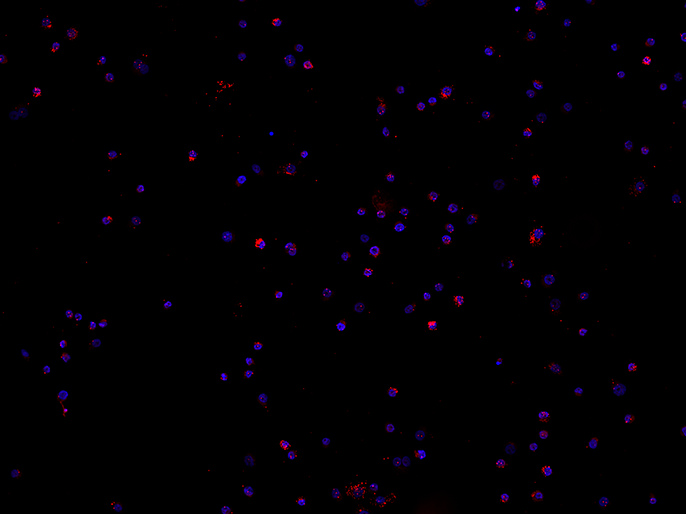

効果がまだ十分に検証されていないNEDD化阻害剤については現在、臨床試験が進められている。ガッターマン博士の作業グループは、この新薬が造血前駆細胞とその分化にどのような影響を与えるかについても研究している。その中でもEGFR(上皮成長因子受容体)のPLA(近接ライゲーションアッセイ)は細胞表面での受容体のホモ二量体化を検出し、その結果、細胞内部で受容体のリン酸化反応が起きるため、細胞増殖の観点からのシグナル伝達効果がある。インタビューを行った時点では初期の結果がまだ発表されておらず、より正確な情報を提供することはできなかった。